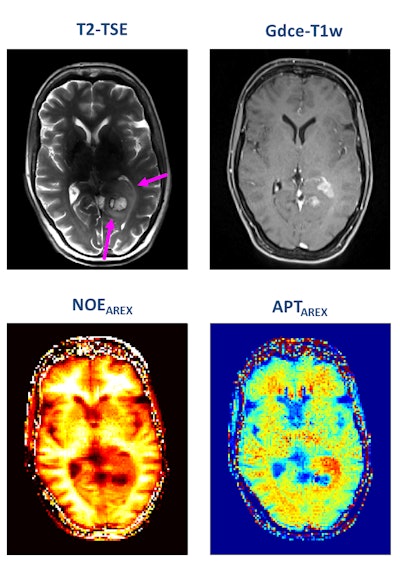

A patient with newly diagnosed glioblastoma underwent relaxation-compensated chemical exchange saturation transfer (CEST) imaging at 7.0 tesla. The protein-weighted CEST contrasts by means of amide proton transfer (APT) and nuclear Overhauser effect (NOE). MRI shows distinct alterations of protein concentrations in the tumor area. While APT signals are markedly increased, NOE-mediated CEST effects drop in the tumor area. The endogenous CEST contrasts have recently proven high potential as novel MR biomarkers to noninvasively assess tumor characteristics and prognosis. (See: Paech D, Windschuh J, Oberhollenzer J, et al, Assessing the predictability of IDH mutation and MGMT methylation status in glioma patients using relaxation-compensated multi-pool CEST MRI at 7.0 T, Neuro-Oncology, November 2018, Vol. 20:12, pp. 1661-1671, and Regnery S, Adeberg S, Dreher C, et al, Chemical exchange saturation transfer MRI serves as predictor of early progression in glioblastoma patients, Oncotarget, June 2018, Vol. 9:47, pp. 28772-28783.) Image courtesy of Dr. Heinz-Peter Schlemmer.

A patient with newly diagnosed glioblastoma underwent relaxation-compensated chemical exchange saturation transfer (CEST) imaging at 7.0 tesla. The protein-weighted CEST contrasts by means of amide proton transfer (APT) and nuclear Overhauser effect (NOE). MRI shows distinct alterations of protein concentrations in the tumor area. While APT signals are markedly increased, NOE-mediated CEST effects drop in the tumor area. The endogenous CEST contrasts have recently proven high potential as novel MR biomarkers to noninvasively assess tumor characteristics and prognosis. (See: Paech D, Windschuh J, Oberhollenzer J, et al, Assessing the predictability of IDH mutation and MGMT methylation status in glioma patients using relaxation-compensated multi-pool CEST MRI at 7.0 T, Neuro-Oncology, November 2018, Vol. 20:12, pp. 1661-1671, and Regnery S, Adeberg S, Dreher C, et al, Chemical exchange saturation transfer MRI serves as predictor of early progression in glioblastoma patients, Oncotarget, June 2018, Vol. 9:47, pp. 28772-28783.) Image courtesy of Dr. Heinz-Peter Schlemmer.Numerous other biomarkers, many of which are functional, are associated with tumors, and these can be quantified with MRI. He pointed out that certain functional biomarkers are readily available, but they have not yet been standardized, and this limits their application at present. Quantification of lesion perfusion over time is a case in point.